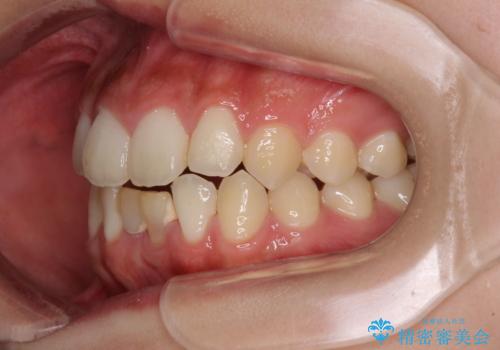

- 下顎前歯に乳歯が残っており、欠損もしていることを気にして来院された患者様です。

舌の突出癖が顕著にあり、上下前歯が非接触となっており、上顎前歯が前方に突出している状態でした。